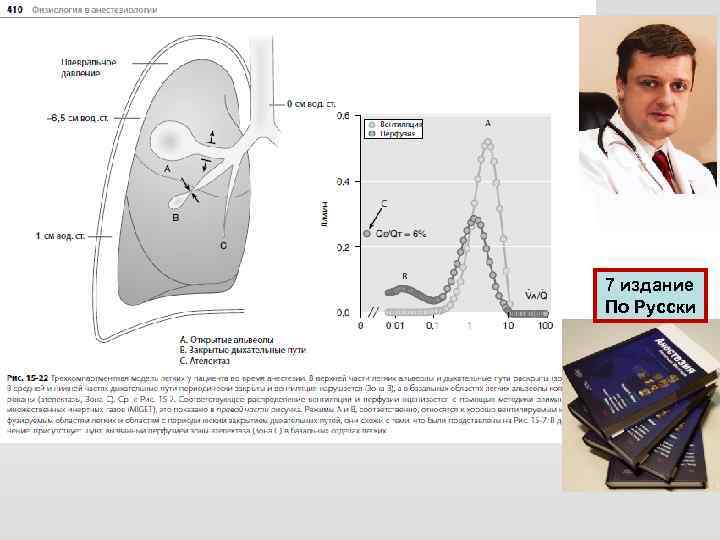

Chepter -19 Respiratory Physiology Göran Hedenstierna

Chepter -19 Respiratory Physiology Göran Hedenstierna

7 издание По Русски

7 издание По Русски

7 издание По Русски

7 издание По Русски